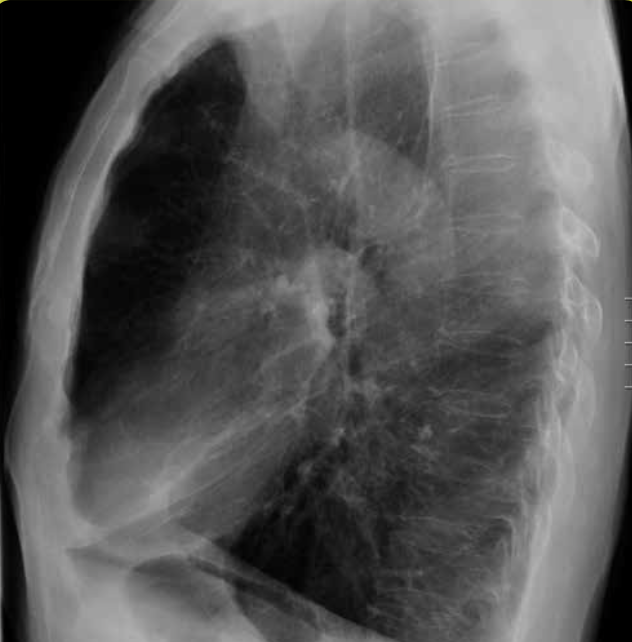

Atelectasia de lóbulo medio con enfisema compensador. Pérdida de volumen del hemitórax derecho.

Atelectasia de lóbulo medio con enfisema compensador. En la proyección lateral se objetiva más claramente el pulmón colapsado.